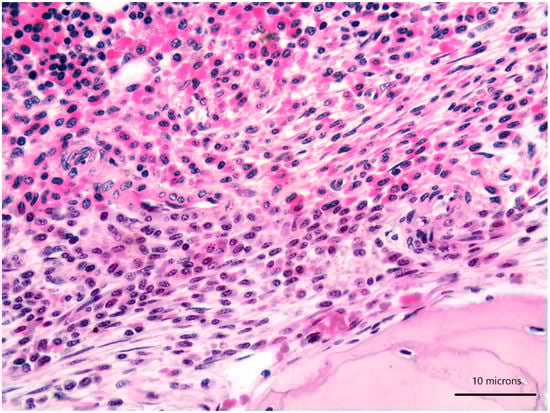

A 79-year-old woman was referred for a long history of peripheral eosinophilia. She underwent right hemicolectomy for colonic polyposis a few years before. Laboratory tests disclosed mild macrocitic anaemia (Hb 10.4 g/dL, MCV 93%) and eosinophilia (leukocytes 3360/mmc, eosinophils 30%). β2 microglobulin (3256 ng/dL; reference range 1010–1730) and serum tryptase (138 ng/L; reference range 0–11.4) were elevated. Serum immunofixation revealed IgA/kappa monoclonal protein (21 g/L). Bence-Jones protein was positive. Bone marrow (BM) biopsy revealed two neoplastic components. Low- and high-power views of haematoxylin and eosin sections showed cohesive paratrabecular aggregates of bland-looking, spindle-shaped cells (Figure 1; Figure 2 lower part) positive for CD117 (Figure 3), tryptase and CD25 representing 20% of marrow cellularity. Aggregates of mature plasma cells (Figure 1; Figure 2 upper part) positive for CD138 (Figure 4), MUM1/IRF4 and kappa light chain occupied 40% of the remaining bone marrow. Bone marrow aspirate confirmed the presence of the two neoplastic components (Figure 5). KITD816V mutation was detected by DHPLC and confirmed by Sanger sequencing; TET2 mutation was identified using DNA sequence analysis on marrow aspirate. Monoallelic deletion of TP53/17p13 and trisomy of ATM/11q23 was detected by FISH analysis on BM enriched with plasma cells using CD138+ magnetic Micro-Beads, respectively, in 39% and 94% of nuclei. RUNX1, ASXL1, SRSF2 and U2AF1 were unmutated. Osteoporosis was identified by full skeletal X-rays and MRI. The case was referred to as SM with concomitant smoldering MM.

Figure 1. Bone marrow biopsy showing paratrabecular aggregates of spindle-shaped cells (lower part) close to clusters of mature plasma cells (upper part) (haematoxylin and eosin, 200× magnification).

Figure 2. High-power view of bone marrow biopsy highlighting morphological details of bland-looking spindle cells (lower part) and mature plasma cells (upper part) (haematoxylin and eosin, 400× magnification).